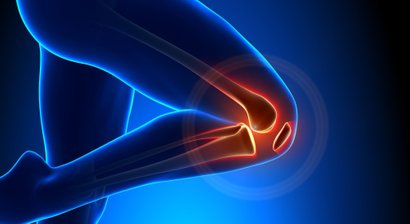

Wenn ein chirurgischer Eingriff notwendig ist, so finden Sie in mir einen Spezialisten für Operationen an Hüfte, Knie und Schulter sowie im Hand- und Fußbereich. Dabei setze ich auf schonende minimal-invasive Methoden.

Knieschmerzen